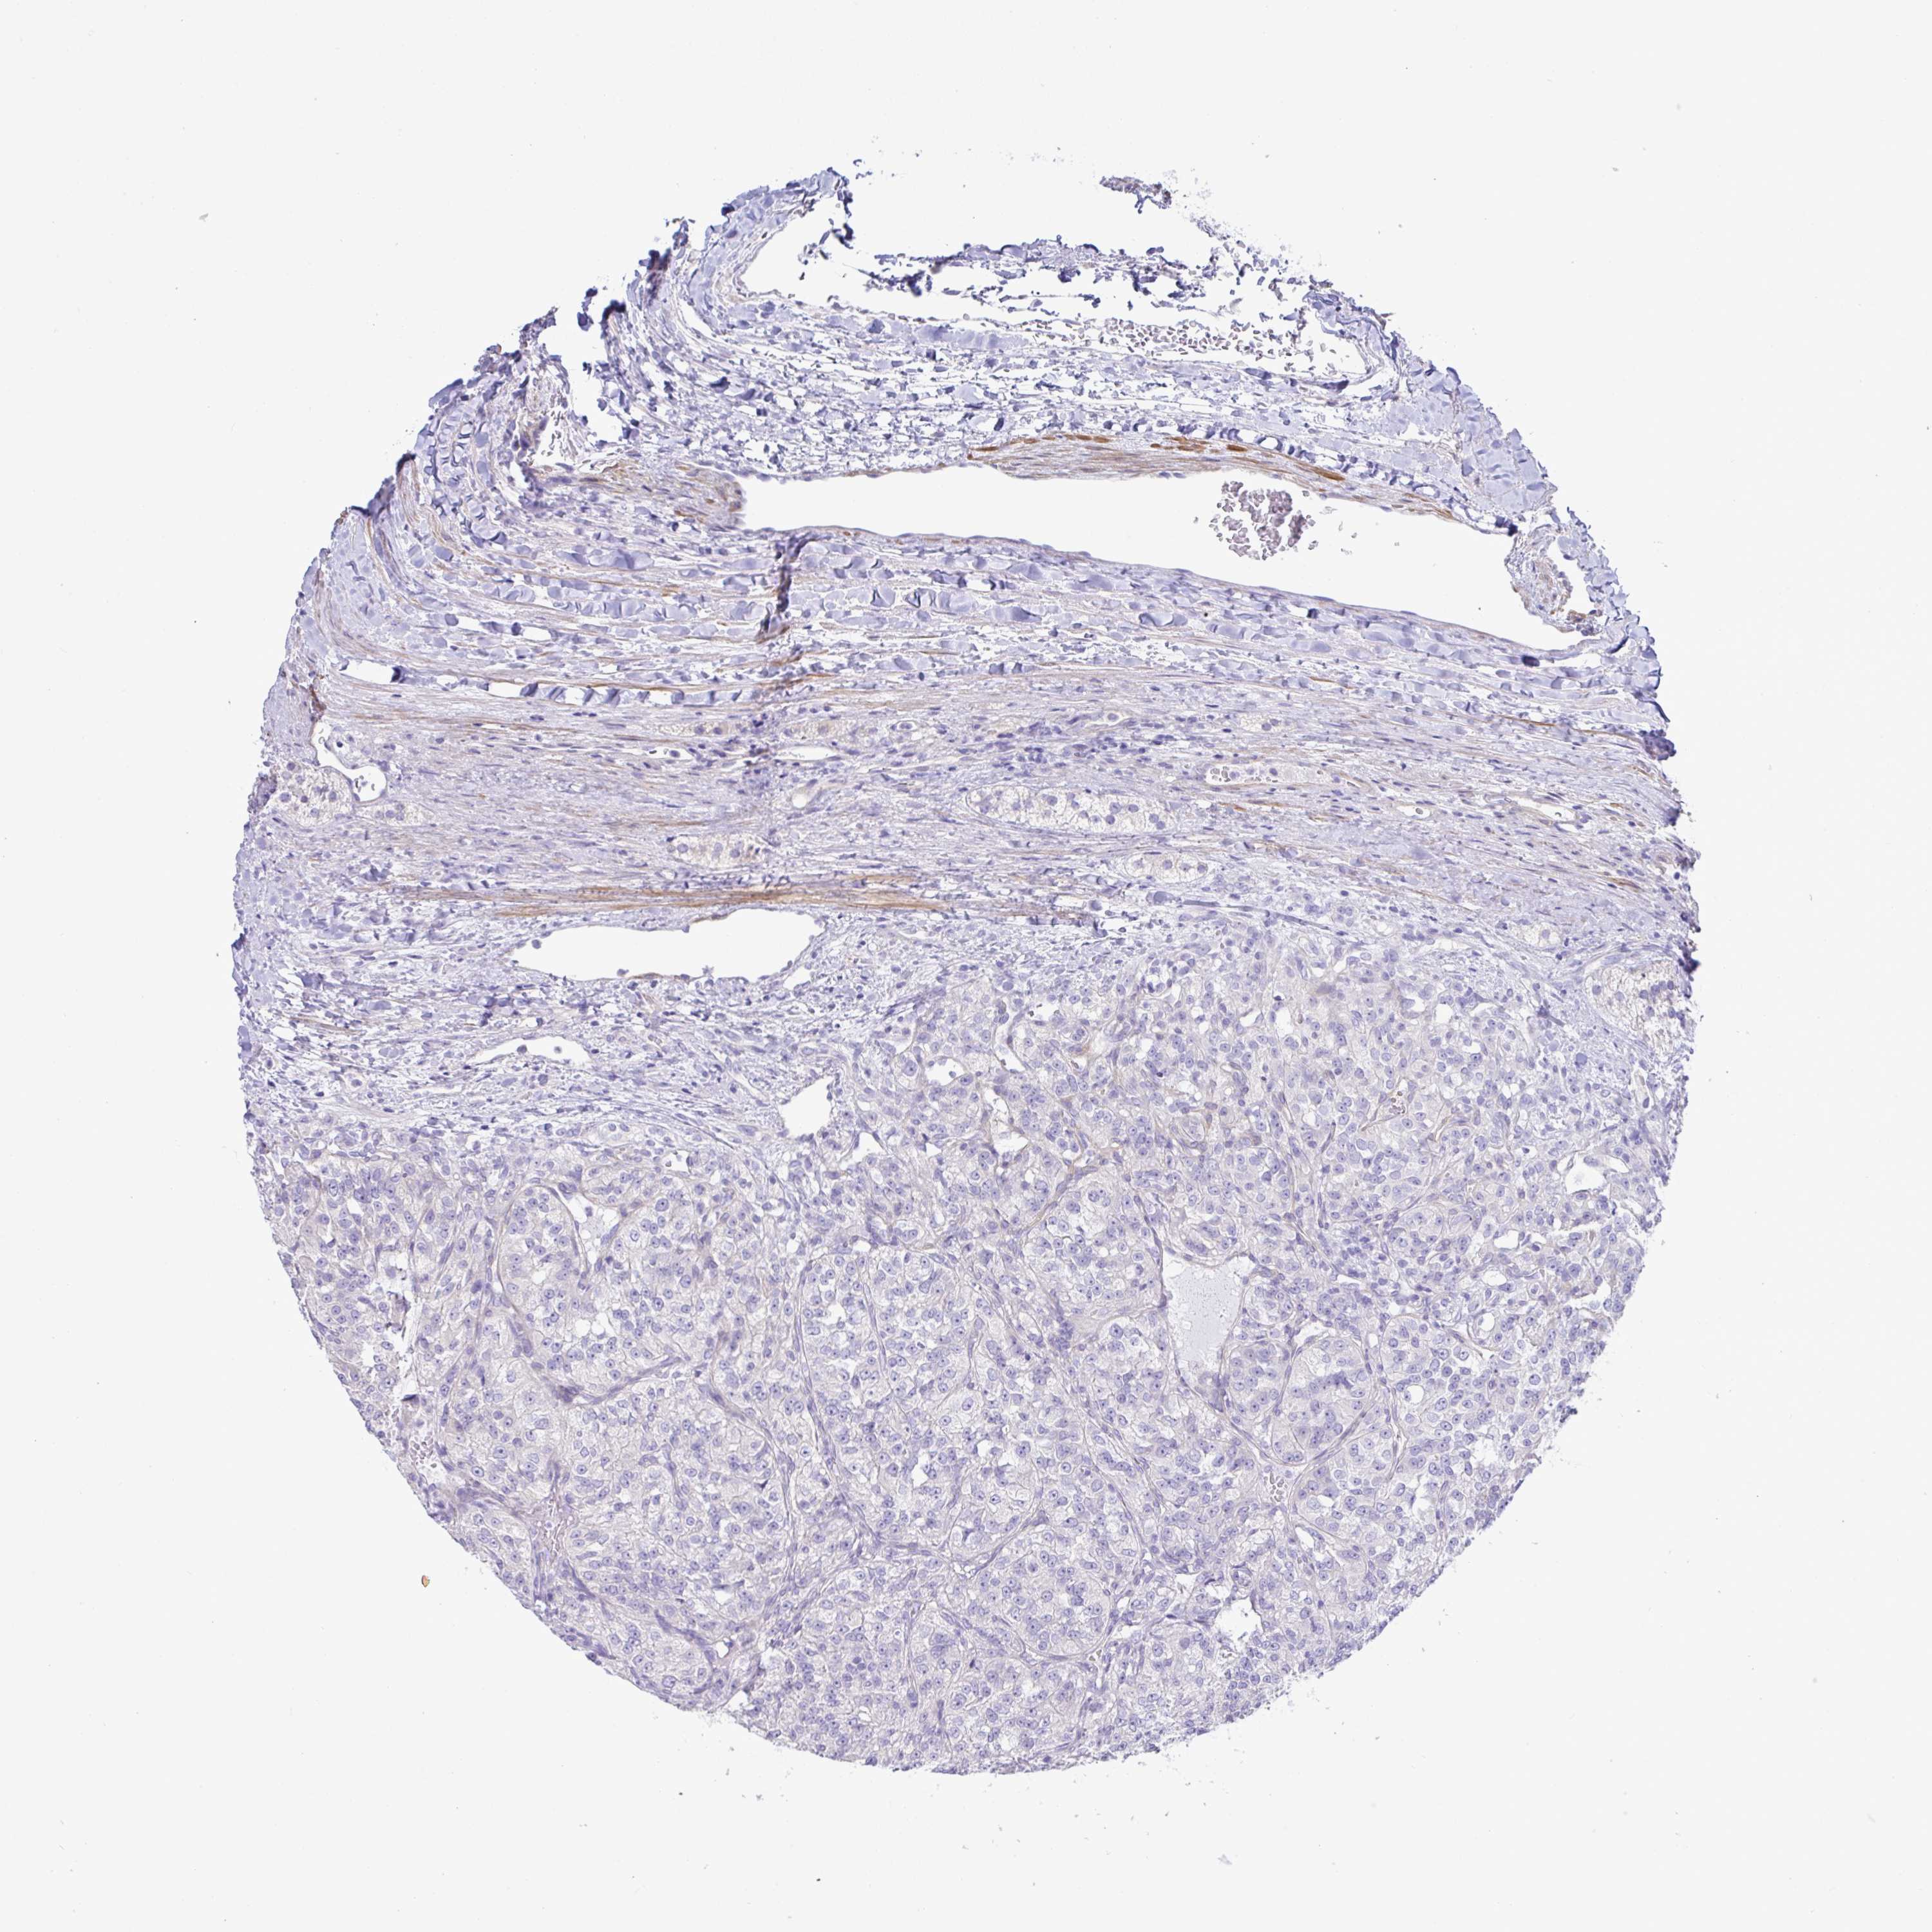

KIDNEY RENAL CLEAR CELL CARCINOMA (VALIDATION) - Interactive survival scatter ploti

The Survival Scatter plot shows the clinical status (i.e. dead or alive) for all individuals in the patient cohort, based on the same data that underlies the corresponding Kaplan-Meier plots. Patients that are alive at last time for follow-up are shown in blue and patients who have died during the study are shown in red.

The x-axis shows the expression levels (FPKM) of the investigated gene in the tumor tissue at the time of diagnosis. The y-axis shows the follow-up time after diagnosis (years). Both axes are complimented with kernel density curves demonstrating the data density over the axes. The top density plot shows the expression levels (FPKM) distribution among dead (red) and alive patients (blue). The right density plot shows the data density of the survived years of dead patients with high and low expression levels respectively, stratified using the cutoff indicated by the vertical dashed line through the Survival Scatter plot. This cutoff is automatically defined based on the FPKM cutoff that minimizes the p-score. The cutoff can be changed by dragging the vertical line or by entering a cutoff value in the square labeled "Current cut-off".

Under the Survival Scatter plot the p-score landscape (black curve; left axis) is shown together with dead median separation (red curve; right axis). Dead median separation is the difference in median mRNA expression between patients who have died with high and low expression, respectively. It is calculated as follows: median FPKM expression of dead patients with high expression - median FPKM expression of dead patients with low expression. This is intended to aid the user in visually exploring custom cutoffs and the associated p-scores and dead median separation.

Individual patient data is displayed and can be filtered by clicking on one or more of the category buttons on the top of the page. Categories describing expression level and patient information include: high, low, alive, dead, female, male and tumor stages. The scale of the x-axis can be toggled between linear and log-scale by clicking on the "x log" button. Mouse-over function shows TCGA ID, patient information and mRNA expression (FPKM) for each patient.

& Survival analysisi

Kaplan-Meier plots summarize results from analysis of correlation between mRNA expression level and patient survival. Patients were divided based on level of expression into one of the two groups "low" (under cut off) or "high" (over cut off). X-axis shows time for survival (years) and y-axis shows the probability of survival, where 1.0 corresponds to 100 percent.

MED11 is potential prognostic, high expression is favorable in Kidney Renal Clear Cell Carcinoma (validation)